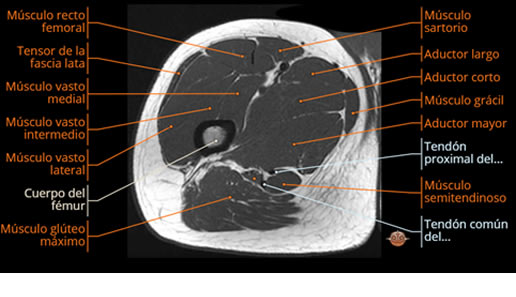

Se realiza estudio de MRI de muslo izquierdo en diferentes planos, con secuencias de Spin Echo, GRE; ponderadas a T1 y a T2, se utilizan pulsos de saturación de grasa y se administra medio de contraste IV a base de Gadolinio en base al peso del paciente.

La diáfisis femoral izquierda muestra reacción perióstica importante, se extiende desde el cuello del fémur, invade trocánteres, diáfisis femoral, medial y distal, es compatible con un proceso infeccioso óseo, el complejo muscular del muslo se ve edematizado.

Desde el punto de vista patológico, el tumor suele localizarse en la diáfisis de huesos largos (como fémur, tibia o húmero), pero también puede afectar costillas, pelvis y columna vertebral. A medida que la lesión progresa, se produce destrucción ósea, formación de tejido blando tumoral y reacción perióstica característica.

La resonancia es la modalidad de elección para valorar la extensión intramedular y la infiltración en tejidos blandos, brindando una imagen más detallada del compromiso tumoral. Los hallazgos característicos incluyen:

Compromiso de la médula ósea adyacente y de estructuras vecinas, como músculos y neurovasculatura.